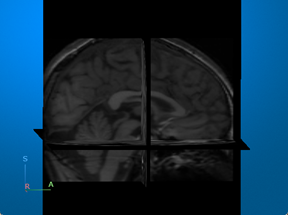

Magnetic resonance imaging (MRI) — Visualize 3-D patient anatomy using a powerful magnetic field and radio waves. |

For an example that uses this image [2][3], see Brain MRI Segmentation Using Pretrained 3-D U-Net Network. |

[2] “NITRC: CANDI Share: Schizophrenia Bulletin 2008: Tool/Resource Info.” Accessed October 17, 2022. https://www.nitrc.org/projects/cs_schizbull08/.

[3] Frazier, J. A., S. M. Hodge, J. L. Breeze, A. J. Giuliano, J. E. Terry, C. M. Moore, D. N. Kennedy, et al. “Diagnostic and Sex Effects on Limbic Volumes in Early-Onset Bipolar Disorder and Schizophrenia.” Schizophrenia Bulletin 34, no. 1 (October 27, 2007): 37–46. https://doi.org/10.1093/schbul/sbm120.